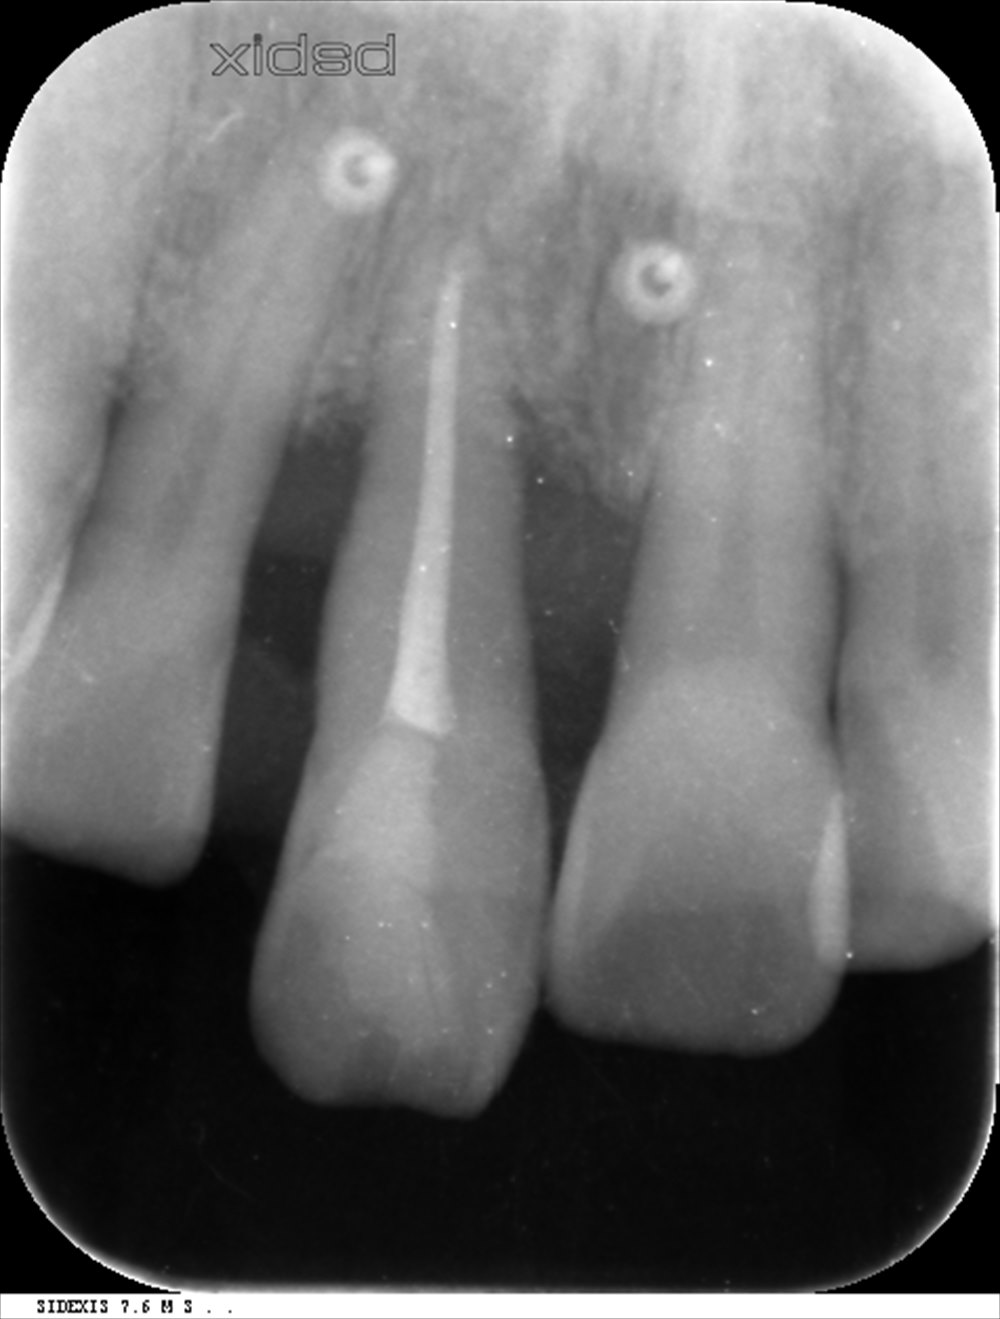

確かにこの歯、レントゲンを見ても前歯は抜けていました。

指で触るとグラグラしていました。

こちらが基本治療を行い、再生治療後6ヶ月のレントゲンです。

再生が認められます。

歯周ポケットも12mmから4mmに改善出血がない状態です。